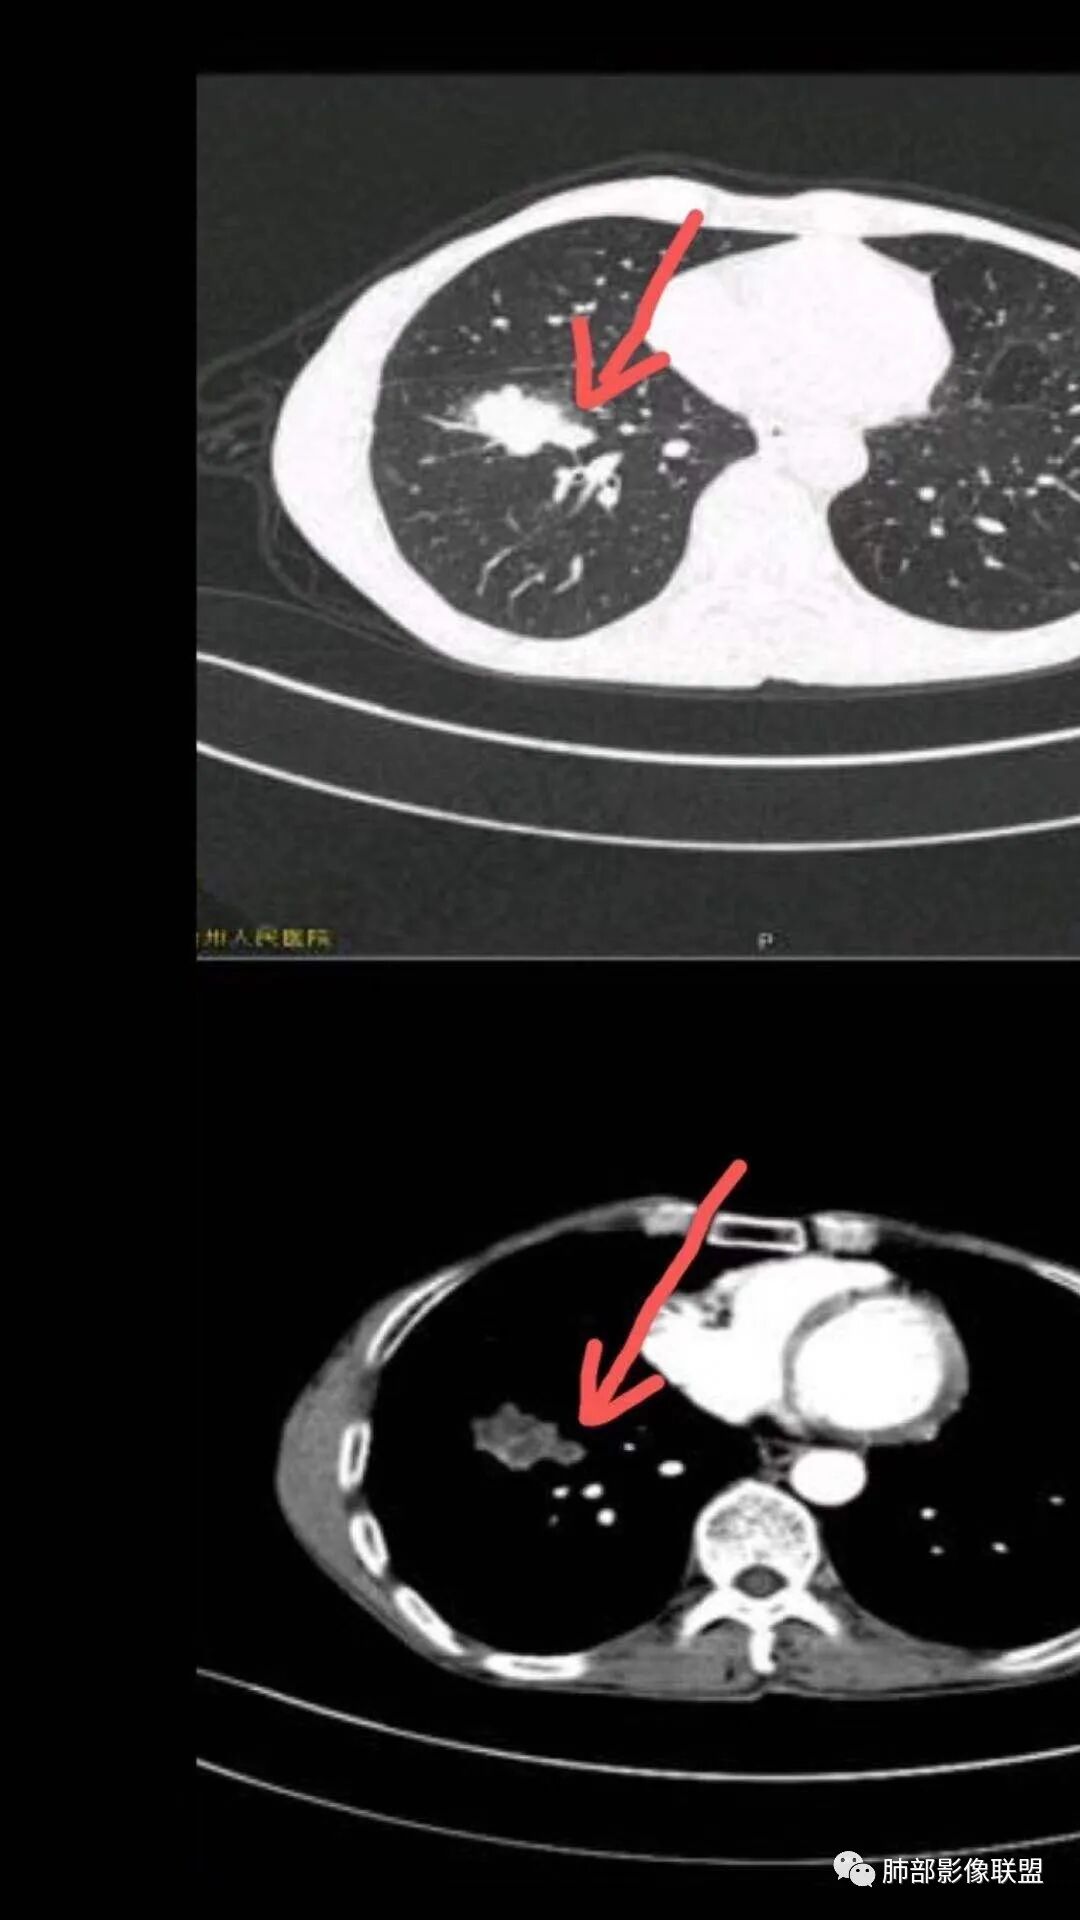

影像表现为 双肺上叶多发索条斑片影,可见支气管牵拉性扩张,考虑为陈旧肺结核纤维硬结灶。右肺下叶前基底段团块影膨隆生长,边界不清,呈分叶,毛刺,胸膜牵拉,支气管截断,中央区坏死明显,但未形成空洞,坏死区边缘光整,不均匀环形强化,隐约见壁结节。纵隔淋巴结肿大伴钙化,病灶远端见阻塞性炎症,结合CYFRA21-1偏高,应想到考虑恶性病变,鳞癌可能性大。

鳞癌的坏死特点

1. 坏死明显,范围大,多,散在

2. 坏死的边界清楚,坏死较彻底,“湖泊样”

3. 病理原因:巢团状生长,中央部分血供不足,并挤压破坏肺血管

4. 壁结节多,是坏死区融合的结果

5. 空洞位于远侧的原因:周围区坏死重

6. 周围区坏死壁常很薄

坏死灶的鉴别

一、炎性病变:

1.结核  整片、均匀薄壁、肺门侧空洞、支气管引流、缺乏壁结节